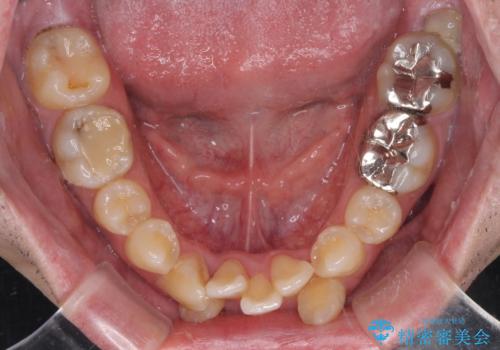

- 上下の八重歯やデコボコを気にして来院された患者様です。

上下ともに八重歯が顕著であったので、上下左右第一小臼歯4本を抜歯し、ワイヤー装置にて矯正治療を行うこととしました。

デコボコが強いことが原因で歯間部に汚れが溜まりやすい状態でしたが、矯正前にできる限り汚れが少なくなるようにブラッシングなどの指導を行い、口腔状態が改善された後にワイヤー装置を装着することとしました。